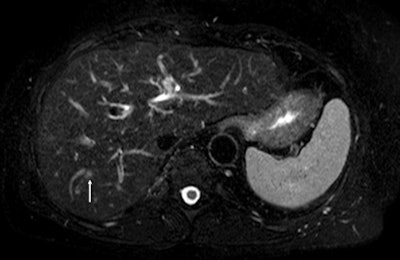

"Four years ago, intraoperative ultrasound sometimes revealed new lesions that had been missed in scans for staging colorectal liver metastasis. Now with diffusion-weighted MRI and the use of hepato-specific MR contrast agents, this is very unlikely to happen," she said, pointing to further details about surgical indications and candidates' prognostic factors to be provided by Dr. Jacques Belghiti, head of the department of hepatobiliary surgery, at the same Paris hospital.

For pretreatment assessment, the focus of Vilgrain's presentation, it is essential to choose the correct treatment plan for the patient, and MRI plays a pivotal role in intrahepatic staging. CT is important for detecting extrahepatic involvement. If the metastatic liver is clearly resectable -- e.g., there are only a few lesions located in a limited, superficial area or confined to one liver lobe and the major vessels are not involved -- then the usual course is neoadjuvant chemotherapy followed by surgery. Imaging is still fundamental for monitoring neoadjuvant chemotherapy response, as surgery performed after no response has a poor prognosis, while even partial response to such therapy improves the prognosis for the resectable patient, she explained. If findings show a borderline case, imaging is still crucial for guiding treatment decisions and monitoring tumor response to chemotherapy.